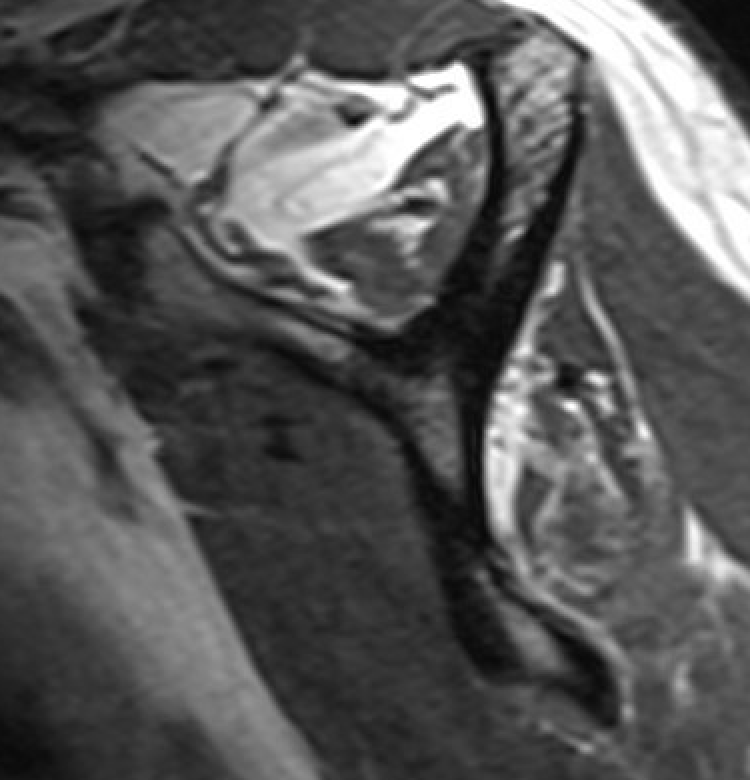

Supraspinatus atrophy

Tangent sign

- sagittal MRI

- line connecting superior coracoid and superior border scapular spine

- if supraspinatus muscle is below line, there is significant atrophy

- positive tangent sign / significant atrophy associated with larger tears / irrepairable tears

Negative tangent / no atrophy Positive tangent / significant supraspinatus atrophy